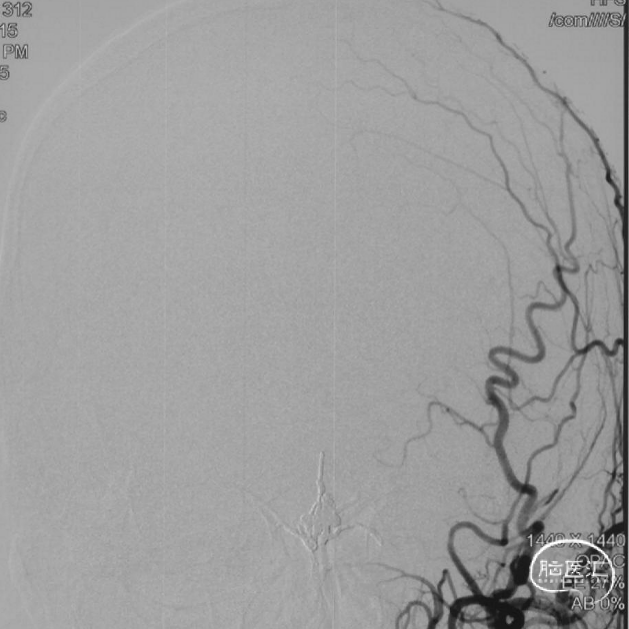

术后三个月造影复查,双侧颈内动脉、颈外动脉造影均未见静脉早显,DAVF治愈。